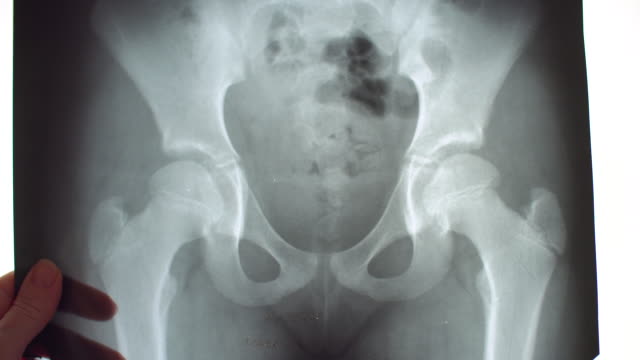

고관절 수술 후 회복에 필요한 시간을 알려드려요. 고관절 수술은 고관절의 변화로 인한 통증 및 기능 장애를 개선하기 위해 수술적인 처리를 하고, 수술 후 환자들은 회복 기간을 거치게 됩니다.

이 글에서는 고관절 수술 후 회복 기간과 주의사항에 대해 알려드리도록 하겠습니다.